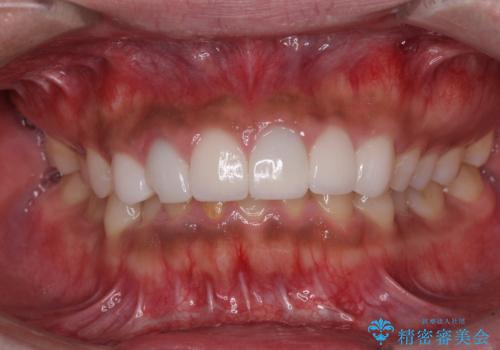

欠けてしまった前歯のセラミック 同じ色合いで再製作

- 前歯のセラミッククラウンが欠けてしまったとのことで来院された患者様です。

周りの他の歯もセラミッククラウンやラミネートベニアが装着されていたため、欠けてしまったクラウンを丁寧に取り外し、同じような色合いとなるように製作することとしました。

欠けたセラミッククラウンを丁寧に外して技工所に送ったことで、元のセラミッククラウン同様の色合いとなり、自然な仕上がりとなりました。